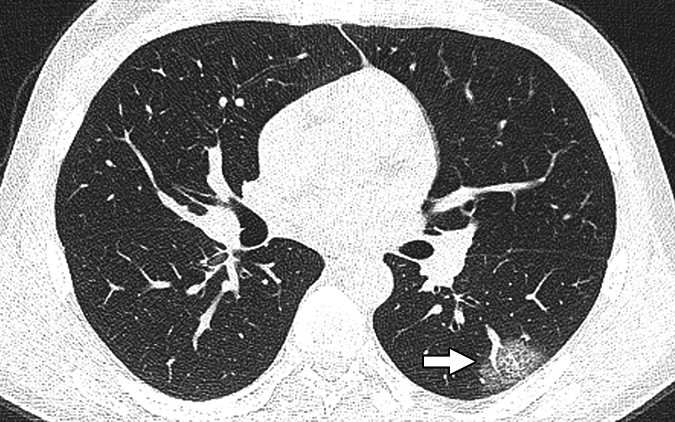

Images show greater rates of emphysema in individuals who smoke marijuana than in those who smoke tobacco-only cigarettes or non-smokers.